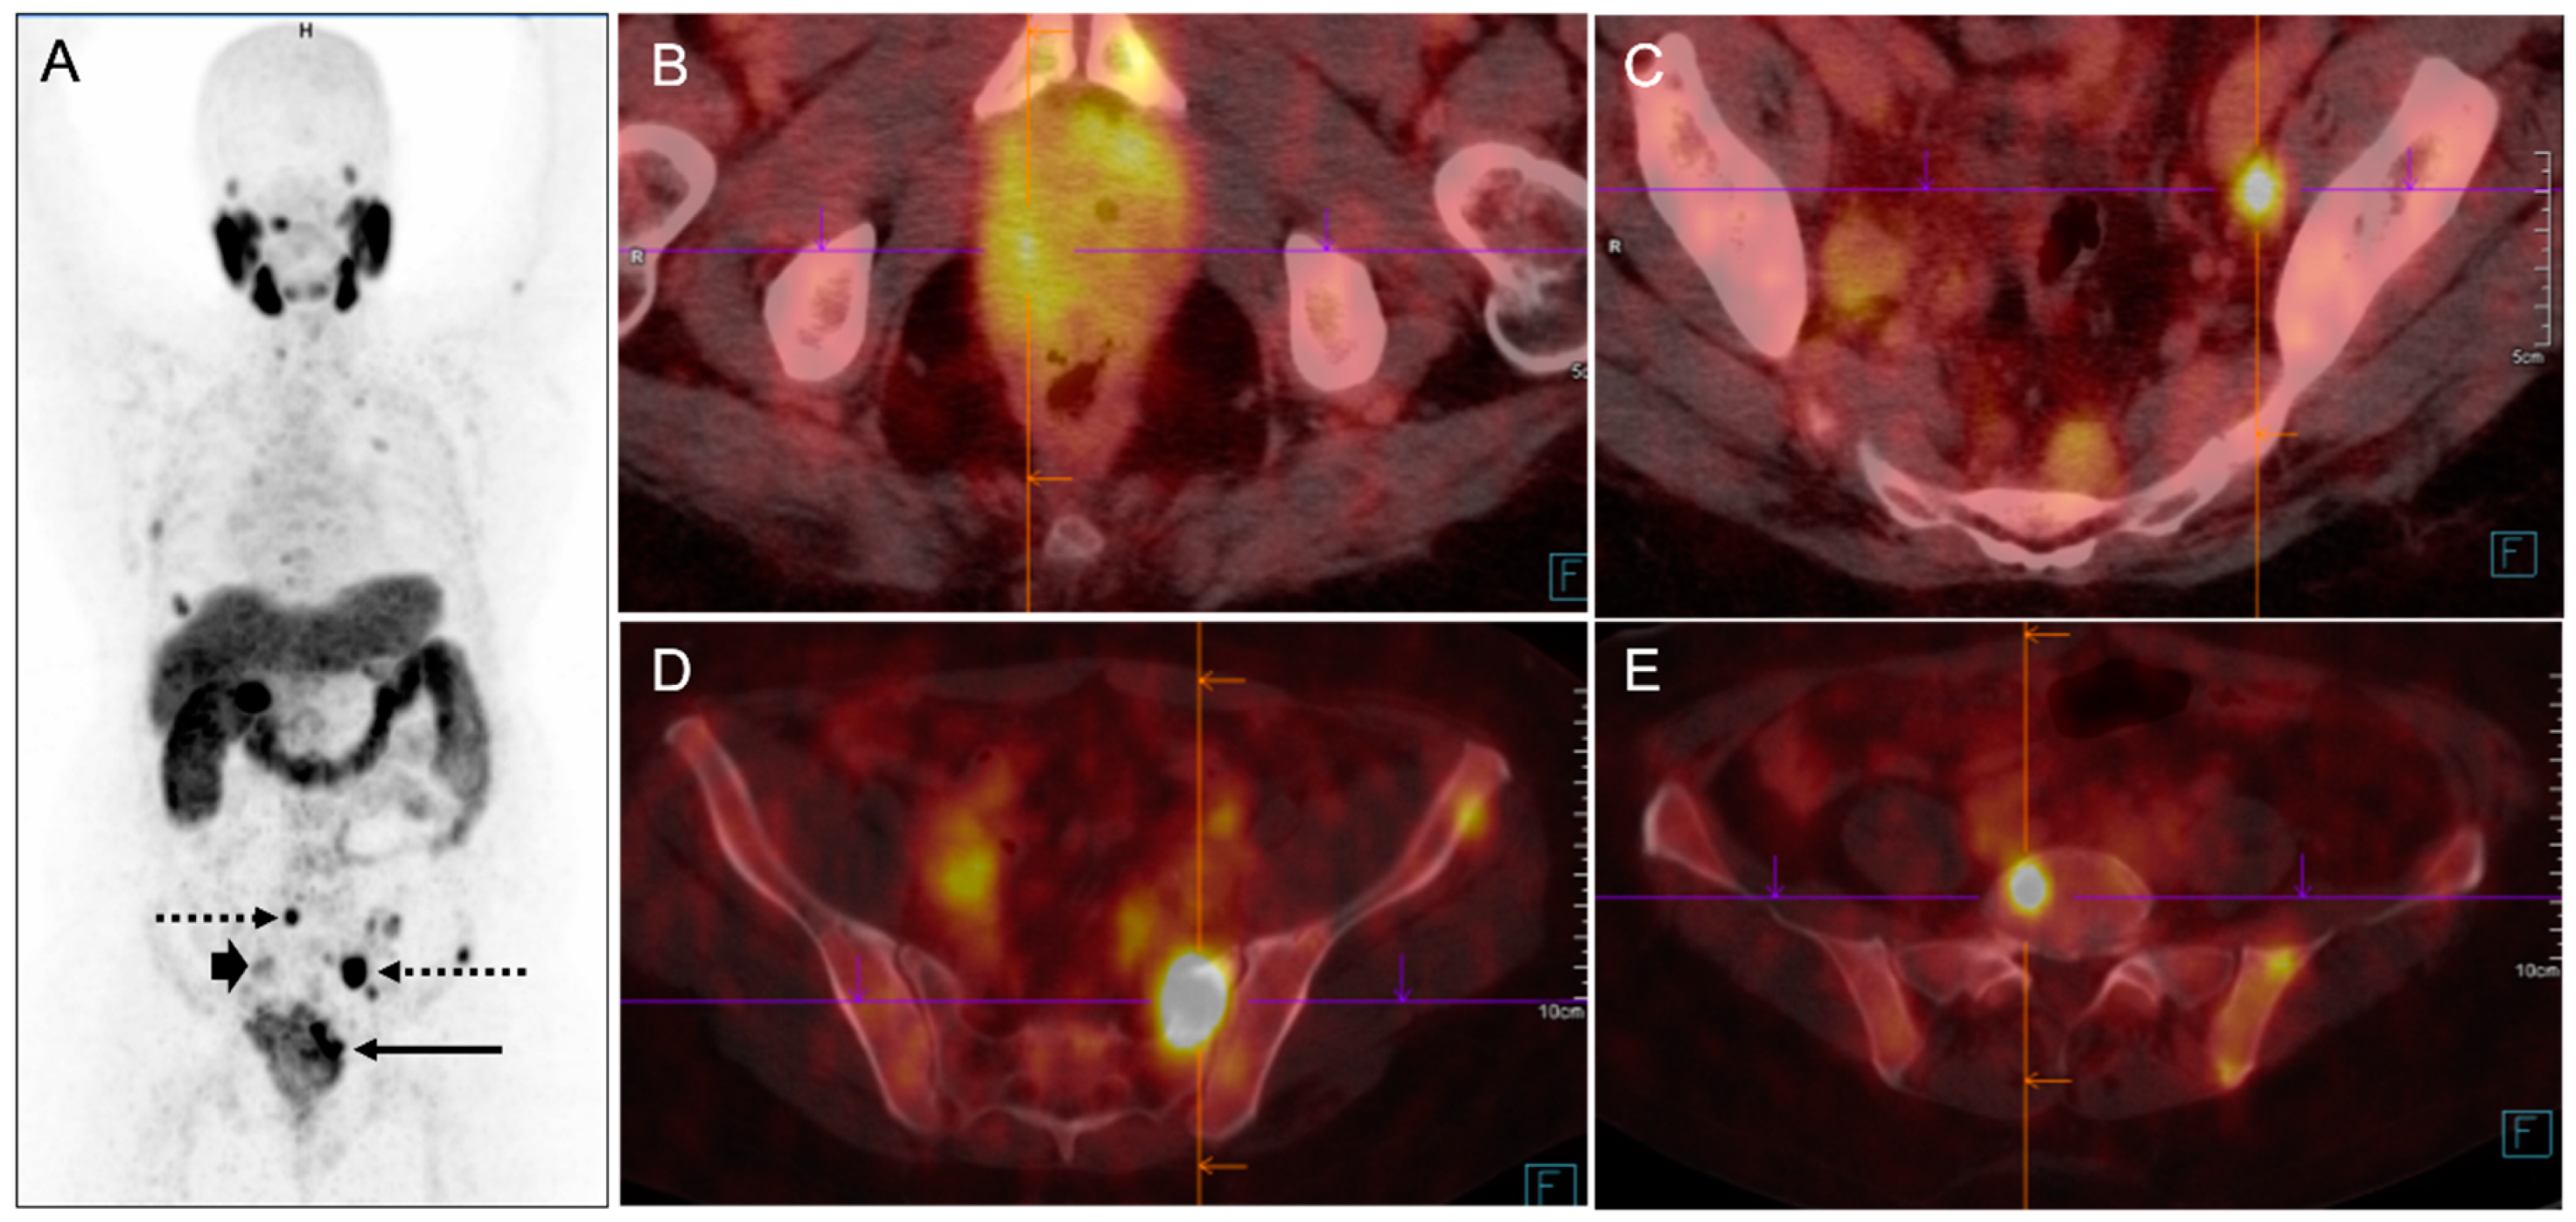

6. Diagnosis with PSMA PET/CT

6.3. Detection of Biochemical Recurrence